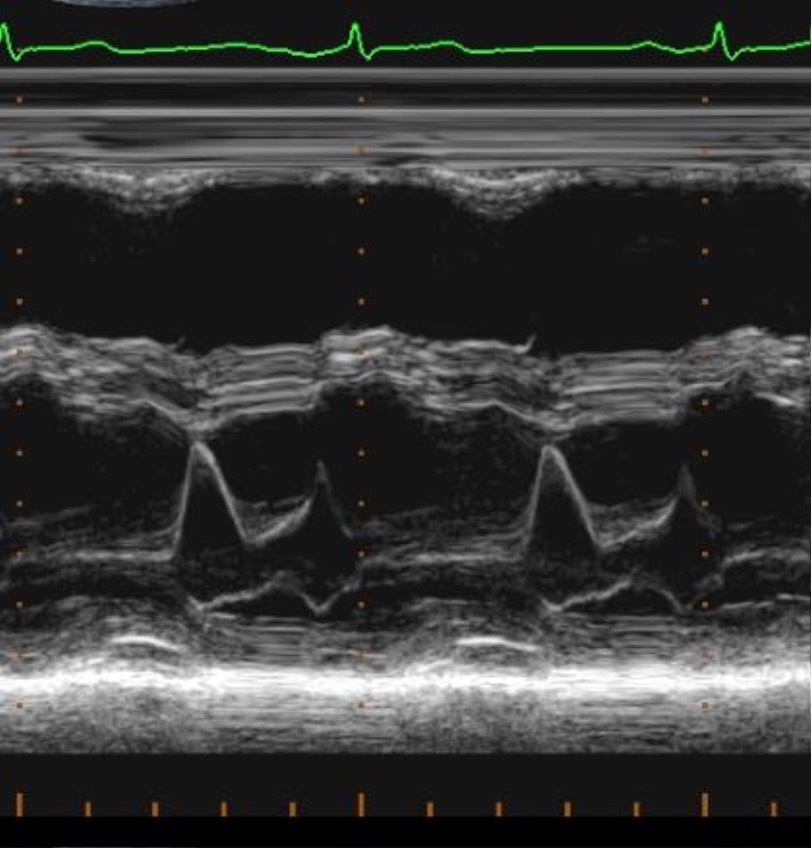

What is the appearance of the MV in m mode?

A

Batman symbol

Q

When taking a M- mode MV, it is important to do what?

Have the cursor at the point of coaptation of the MV leaflets

22

What does the E/A MV values mean? 2

1. E wave = early filling (LV sucking in blood)

2. A wave = Atrial Kick (Atria Contracting)

Label the structures for a MV waves from left to right

1. E wave (Early filling) first peak of the M

2. A wave (Atria Contracting) second peak

What is normal EPSS measurement?

25

How does MV M-mode in dilated cardiomyopathy look like?

Gap between the MV and the IVS when the MV is fulling opening